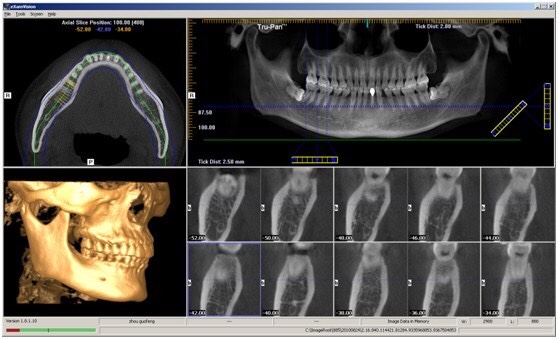

隨著生活水平的提高,人們對(duì)牙科病,牙齒矯形等越來(lái)越重視,口腔曲面斷層攝影在臨床診療中的應(yīng)用越來(lái)越廣泛。為滿足患者及臨床需求,為臨床提供更精確的診斷信息,我院購(gòu)買了KaVo的ORTHOPANTOMOGRAPH OP 3D Pro口腔錐形束計(jì)算機(jī)斷層掃描設(shè)備(CBCT),已安裝調(diào)試投入臨床使用。

CBCT片